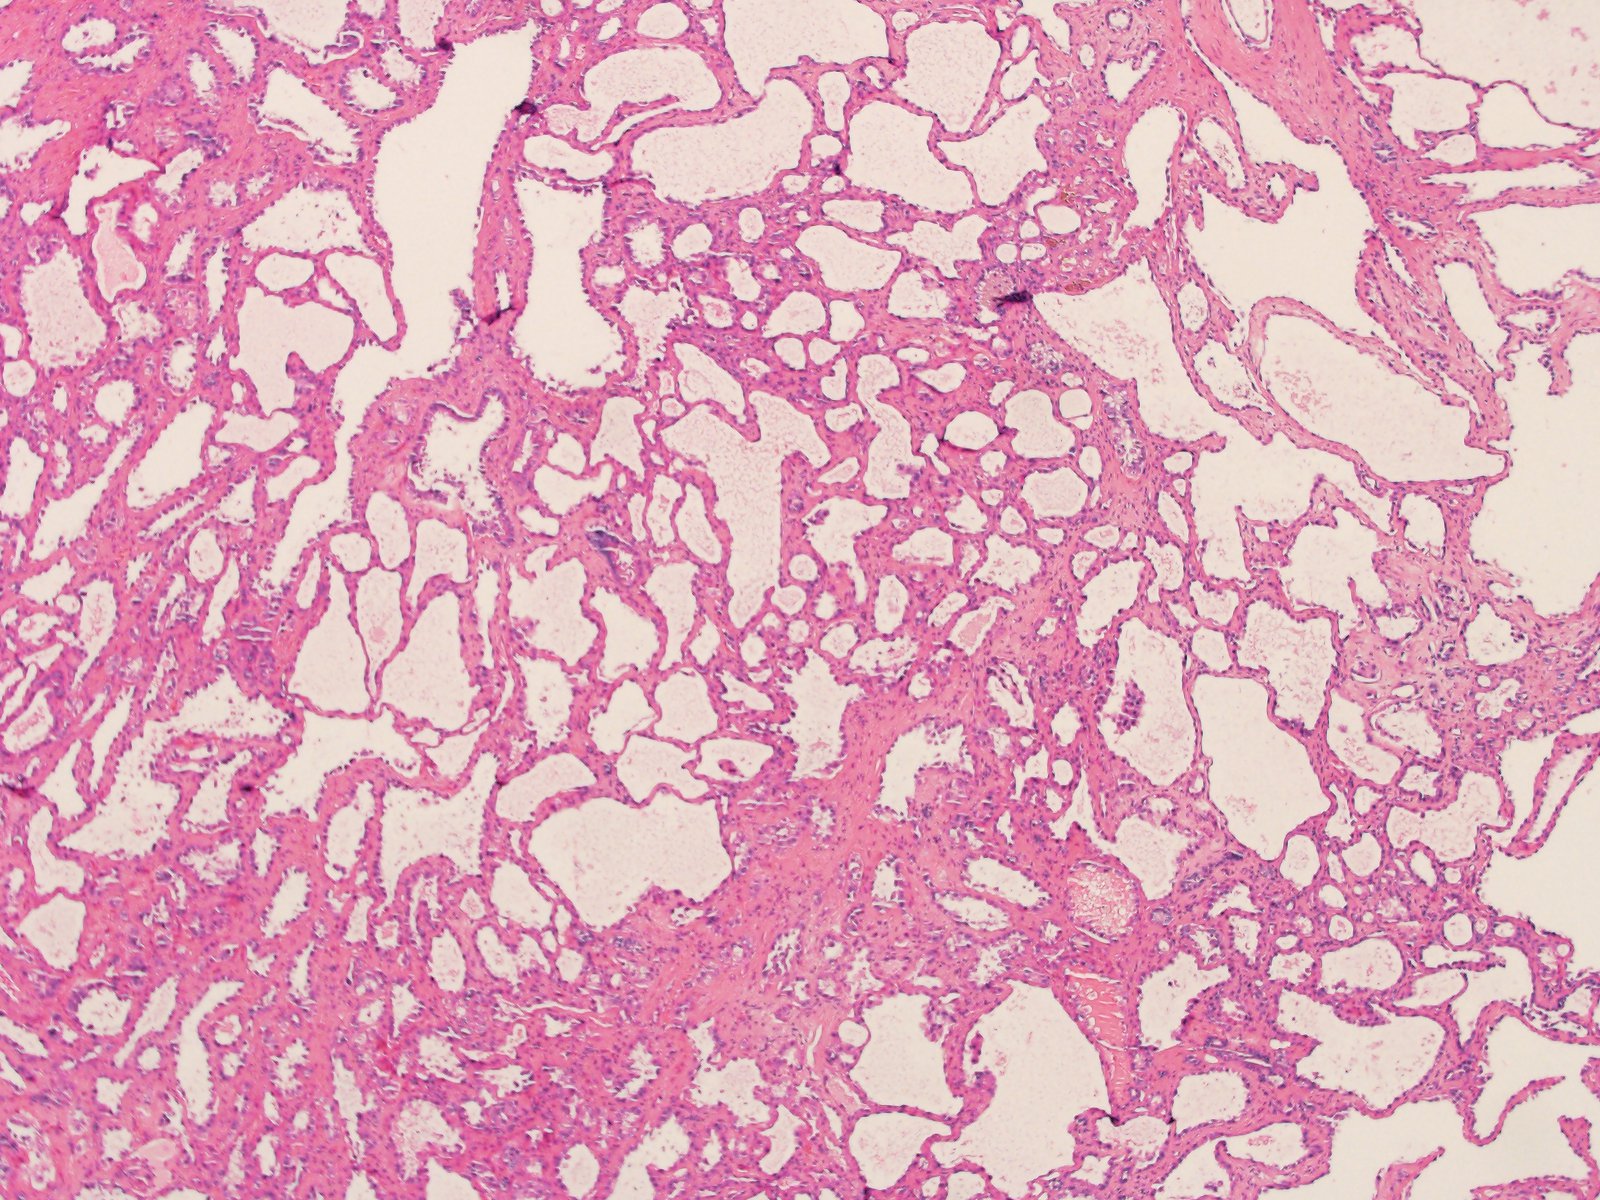

Classification of renal tumors

Case ID: 814